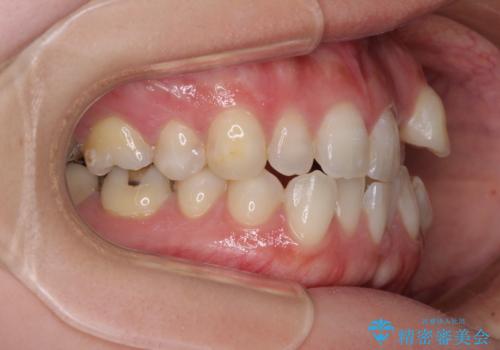

- 左上の八重歯と前歯のデコボコを気にして来院された患者様です。

下顎が左側にズレており、下顎前歯は1歯欠損していたため、左上小臼歯1本を抜歯し、ワイヤー装置にて矯正治療を行うこととしました。